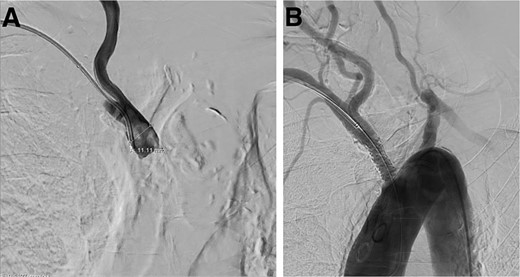

The patient was assessed for endovascular revascularization of the innominate artery. Right radial access and right femoral access were obtained. A pigtail catheter was advanced by the femoral access to obtain an aortic arch image and confirm the location of the catheter at the brachycephalic artery (Fig. 3A). Moreover, the radial access advanced a stiff glide wire, and a large bore catheter was advanced over it. Furthermore, a Gore Viabahn VBX Balloon Expandable Stent (W.L. Gore & Associates, Flagstaff, AZ, USA) was introduced and, under roadmap guidance, crossed the site of obstruction, completing the revascularization (Fig. 3B). The patient was discharged and referred for rehabilitation a few days later with a disappearance of the symptoms.

Digital subtraction angiogram demonstrating: (A) brachiocephalic artery occluded before the stent placement. (B) Brachiocephalic artery opened after the introduction of the Gore Viabahn VBX Balloon Expandable Stent (W.L. Gore & Associates, Flagstaff, AZ, USA).